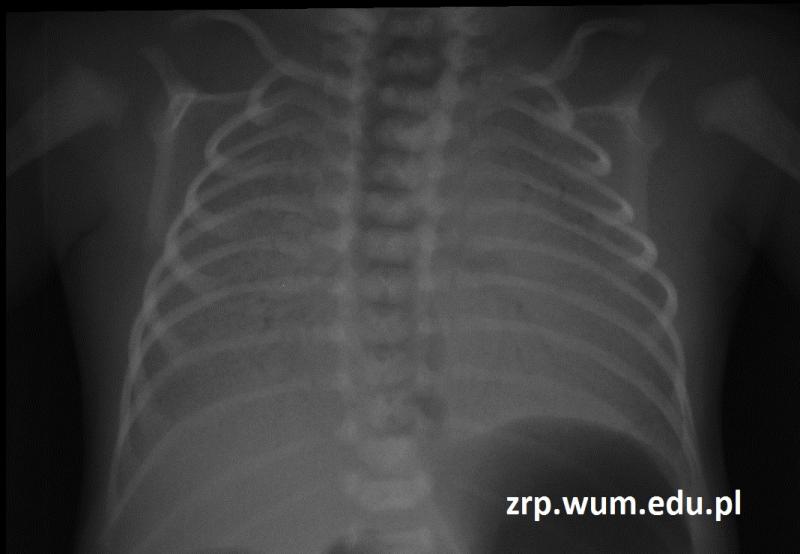

Przypadek 59: Wcześniak w 1. dobie życia, niewydolny oddechowo.

Rozpoznanie: Bezpowietrzne płuca, z bronchogramem powietrznym. Obraz jak w RDS 4 stopnia.